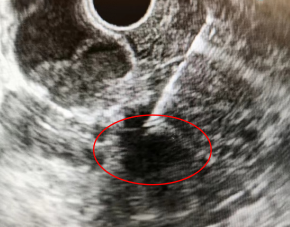

超聲內(nèi)鏡下顯示的病灶

該患者因“反復(fù)發(fā)熱及上腹痛1月余”先后就診于我院感染性疾病科及肝膽胰外科,實(shí)驗(yàn)室檢測(cè)聯(lián)合影像學(xué)檢查未能明確診斷。為進(jìn)一步明確病因,經(jīng)我院消化內(nèi)科會(huì)診后,建議進(jìn)一步完善超聲內(nèi)鏡(EUS)檢查。經(jīng)EUS檢查后,考慮為膽總管下端占位性病變,伴膽總管截?cái)唷⒐W琛⒀装Y改變。遂進(jìn)一步通過(guò)EUS-FNA獲取占位性病變的組織病理學(xué)標(biāo)本,隨后我院病理科結(jié)合組織病理學(xué)表現(xiàn)和免疫組織化學(xué)染色結(jié)果,明確診斷為腺癌,考慮膽管來(lái)源。